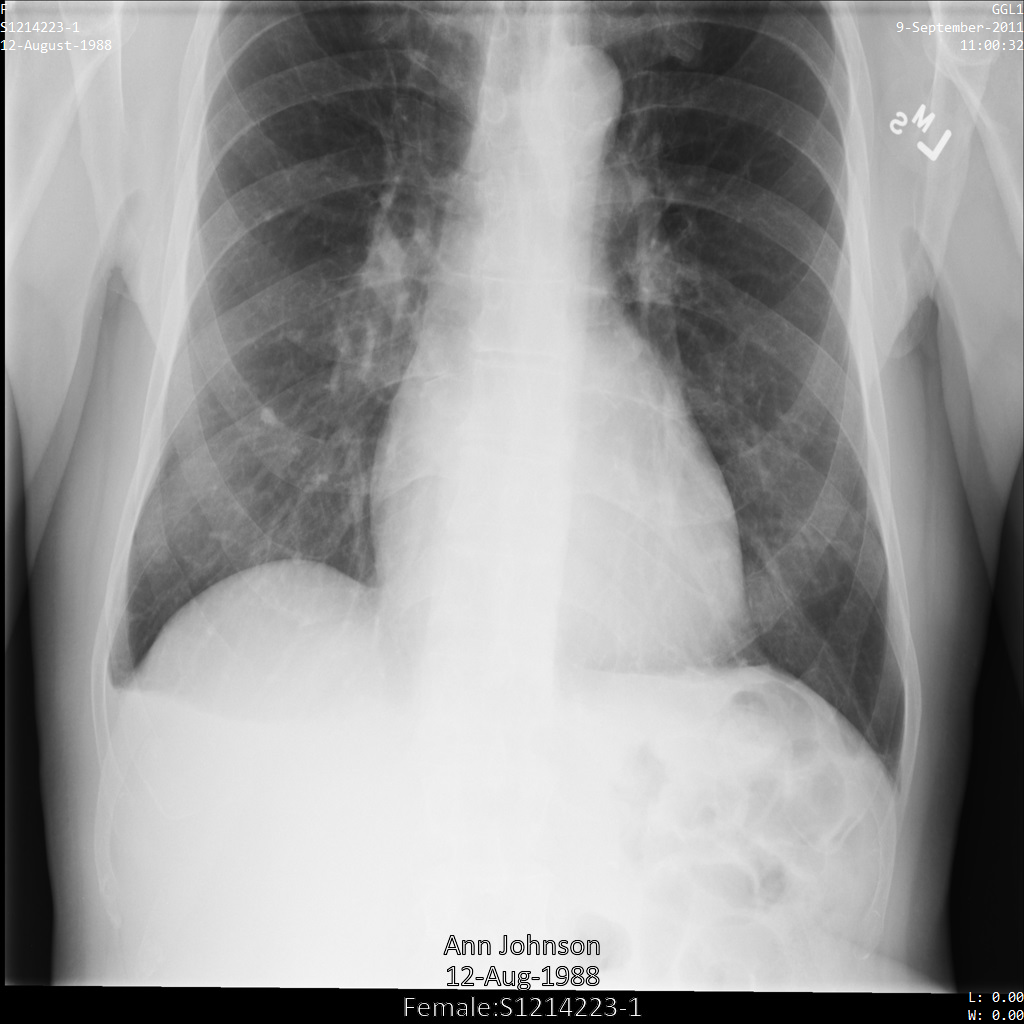

En cada una de las siguientes secciones, se proporcionan ejemplos de cómo desidentificar datos de DICOM mediante varios métodos. Se proporciona un resultado de la imagen desidentificada en cada muestra. En cada muestra, se usa la siguiente imagen original como su entrada:

Puedes comparar la imagen de salida de cada operación de desidentificación con esta imagen original para ver los efectos de la operación.

Después de enviar la imagen a la API de Cloud Healthcare mediante el perfil DEIDENTIFY_TAG_CONTENTS, la imagen aparece de la siguiente manera.

Observa los siguientes cambios:

- Los nombres en la esquina superior izquierda y en la esquina superior derecha de la imagen se transformaron con una

CryptoHashConfig - Las fechas en la esquina superior izquierda y derecha de la imagen se transformaron con un

DateShiftConfig